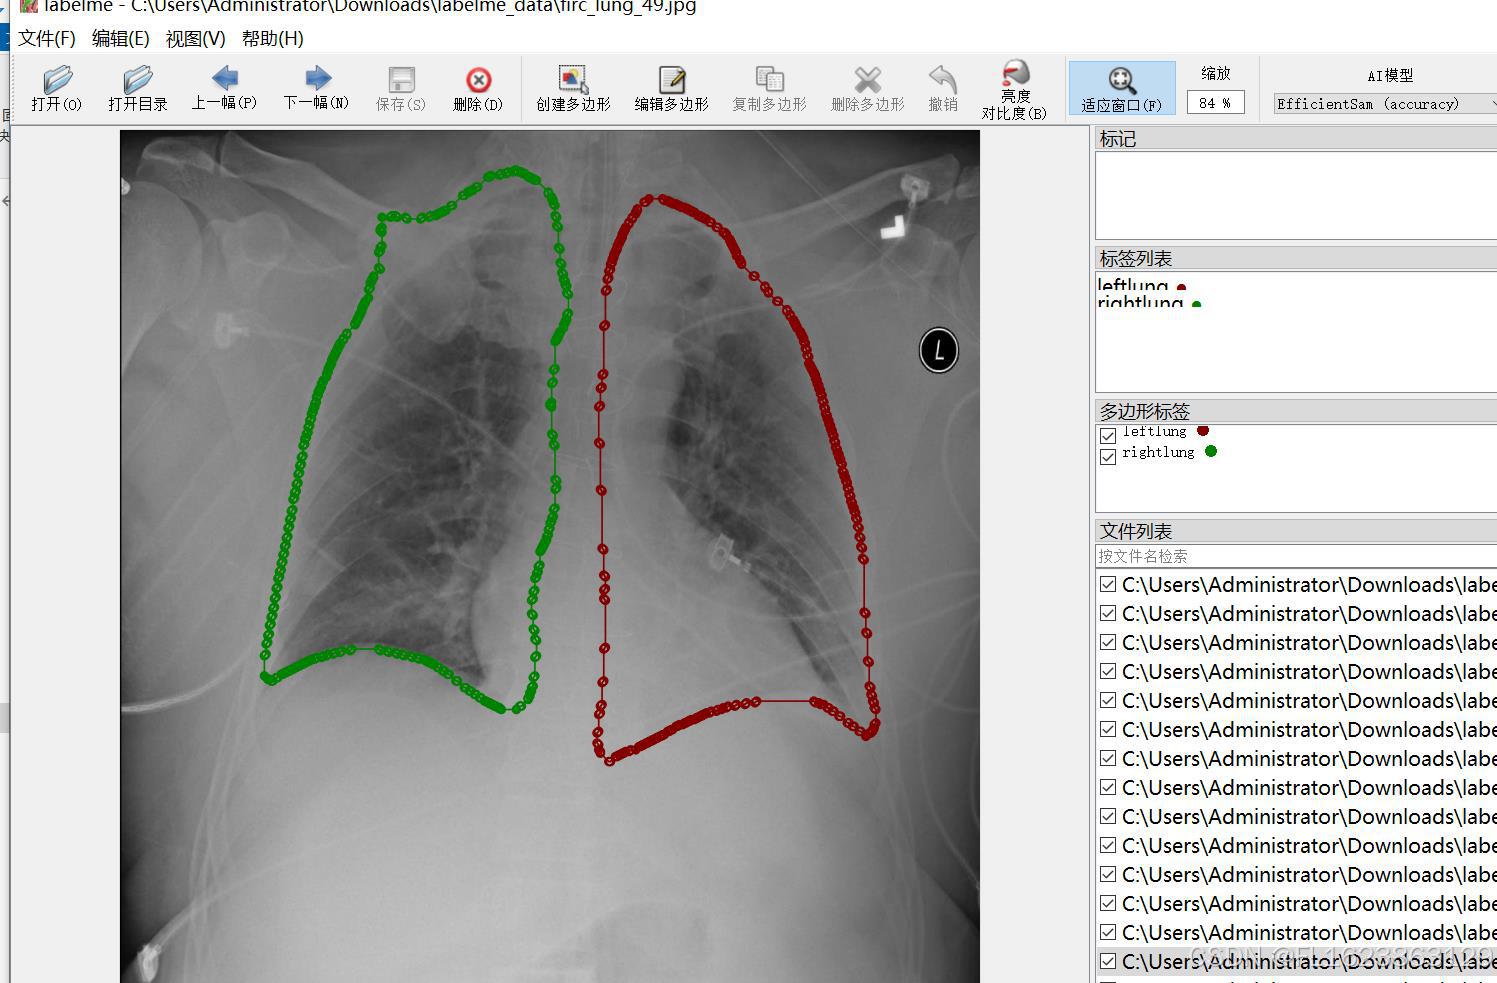

标注类别名称:["leftlung","rightlung"]

标注规则:对类别进行画多边形框polygon

图片预览:

标注例子